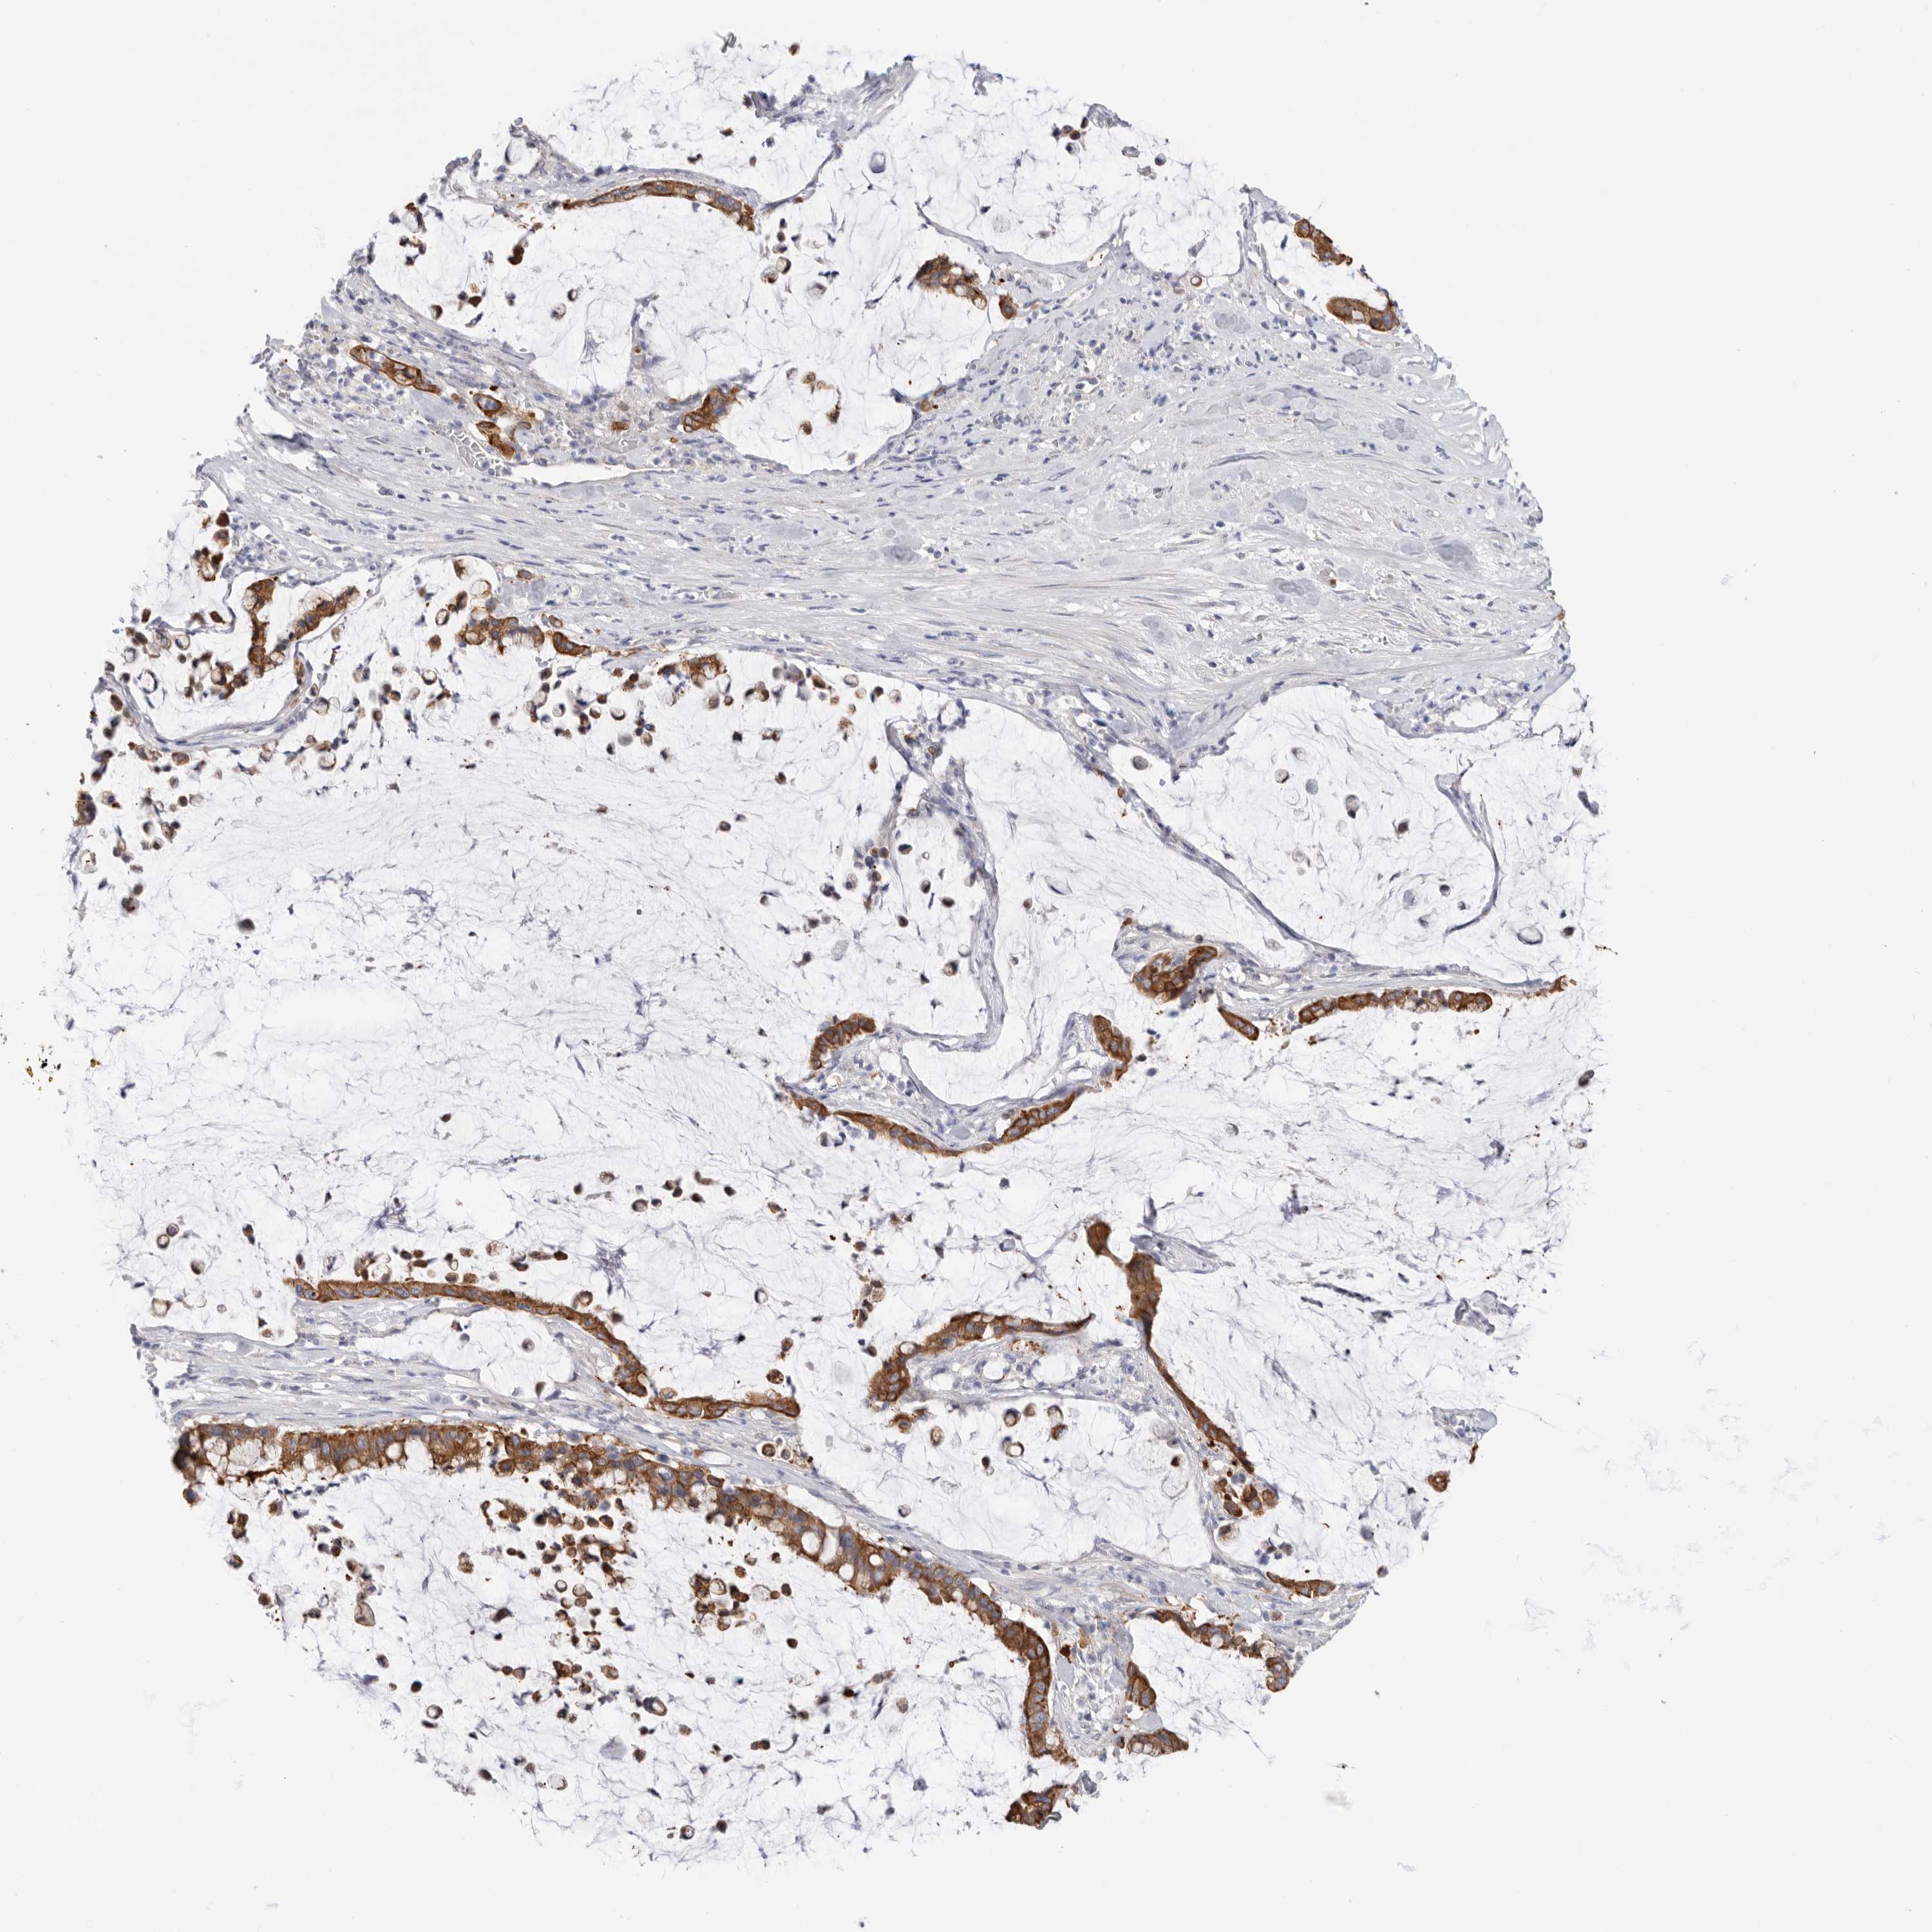

PANCREATIC CANCER - Protein expressioni

A mouse-over function shows sample information and annotation data. Click on an image to view it in a full screen mode. Samples can be filtered based on level of antibody staining by selecting one or several of the following categories: high, medium, low and not detected. The assay and annotation is described here.

Note that samples used for immunohistochemistry by the Human Protein Atlas do not correspond to samples in the TCGA dataset.

Antibody stainingi

Antibody staining in the annotated cell types in the current human tissue is reported as not detected, low, medium, or high, based on conventional immunohistochemistry profiling in selected tissues. This score is based on the combination of the staining intensity and fraction of stained cells.

Each image is clickable and will lead to virtual microscopy that enables deeper exploration of all samples and also displays staining intensity scores, fraction scores and subcellular localization as well as patient and tissue information for each sample.

Antibody HPA027124

Antibody HPA027130

Staining

High

Medium

Low

Not detected

Intensity

Strong

Moderate

Weak

Negative

Quantity

>75%

75%-25%

<25%

None

Location

Nuclear

Cytoplasmic/membranous

Cytoplasmic/membranous,nuclear

Adenocarcinoma, NOS